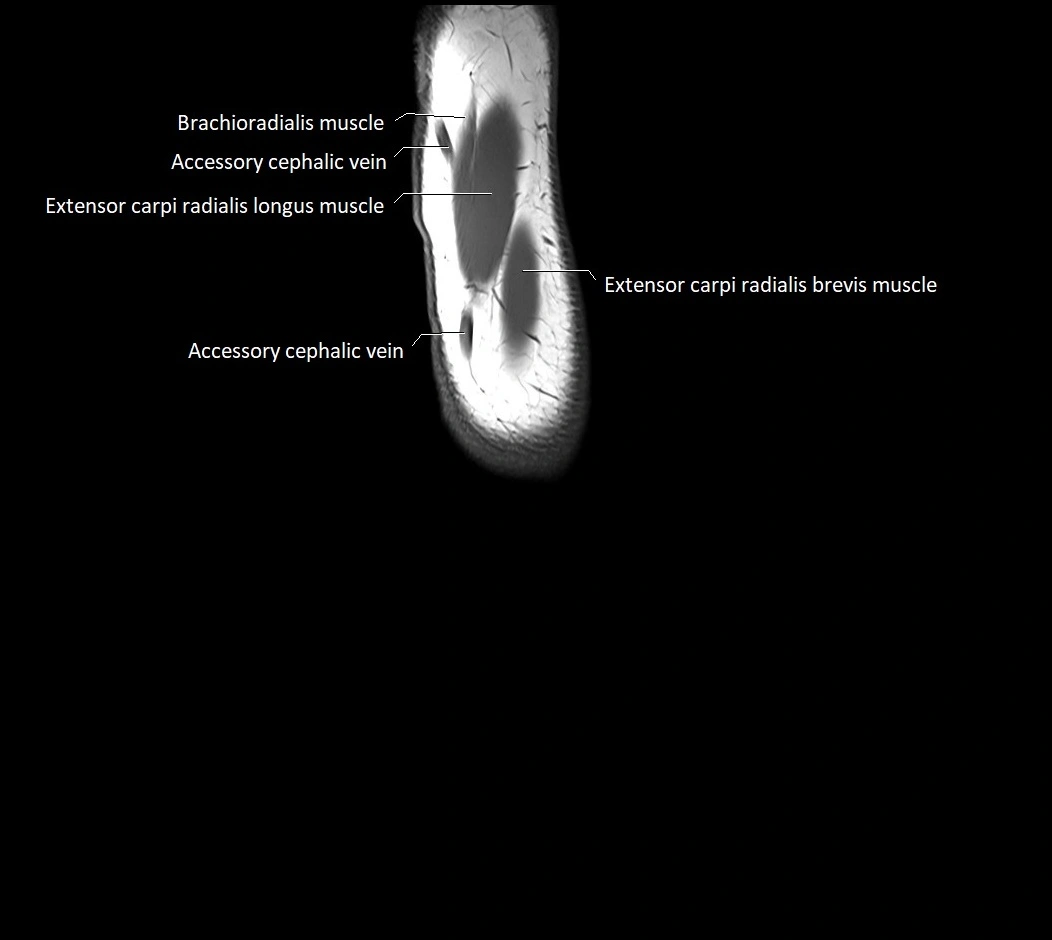

MRI images

image